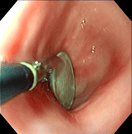

異物:1円玉

異物:裁縫針

異物:梅干しの種

食道内異物回収後